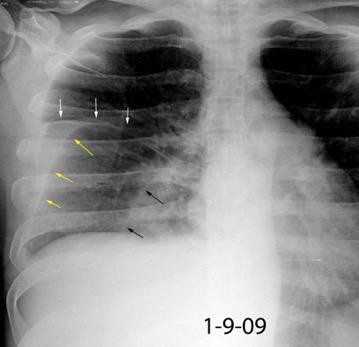

Signos en decúbito supino

175 cc

Dec. supino

Líquido en cisura horizontal y accesoria derecha